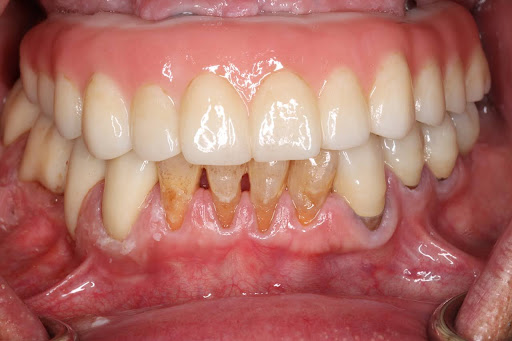

症例